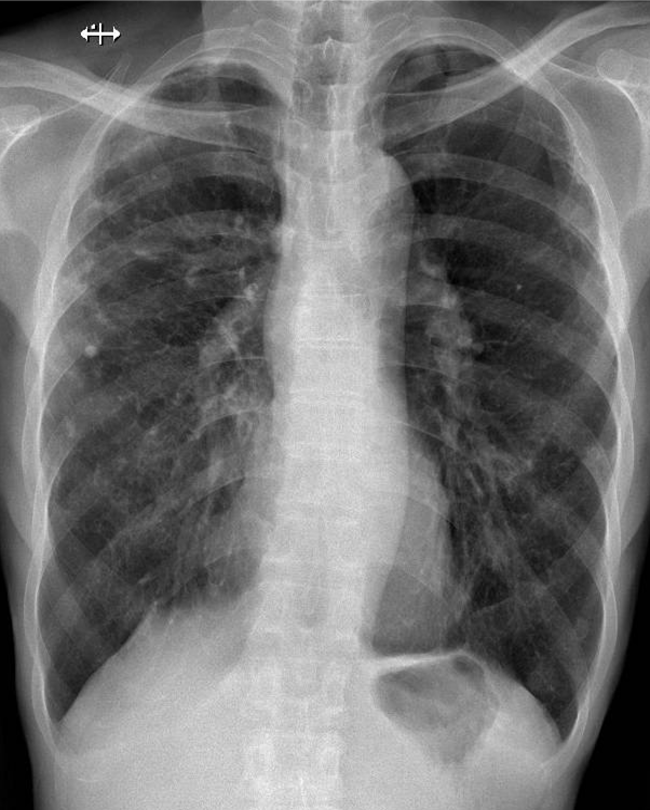

Hãy phân tích tình huống NAM 73 tuổi

1-Xơ thâm nhiễm + khí phế thũng rải rác hai phổi 2-Dày dính màng phổi hai bên